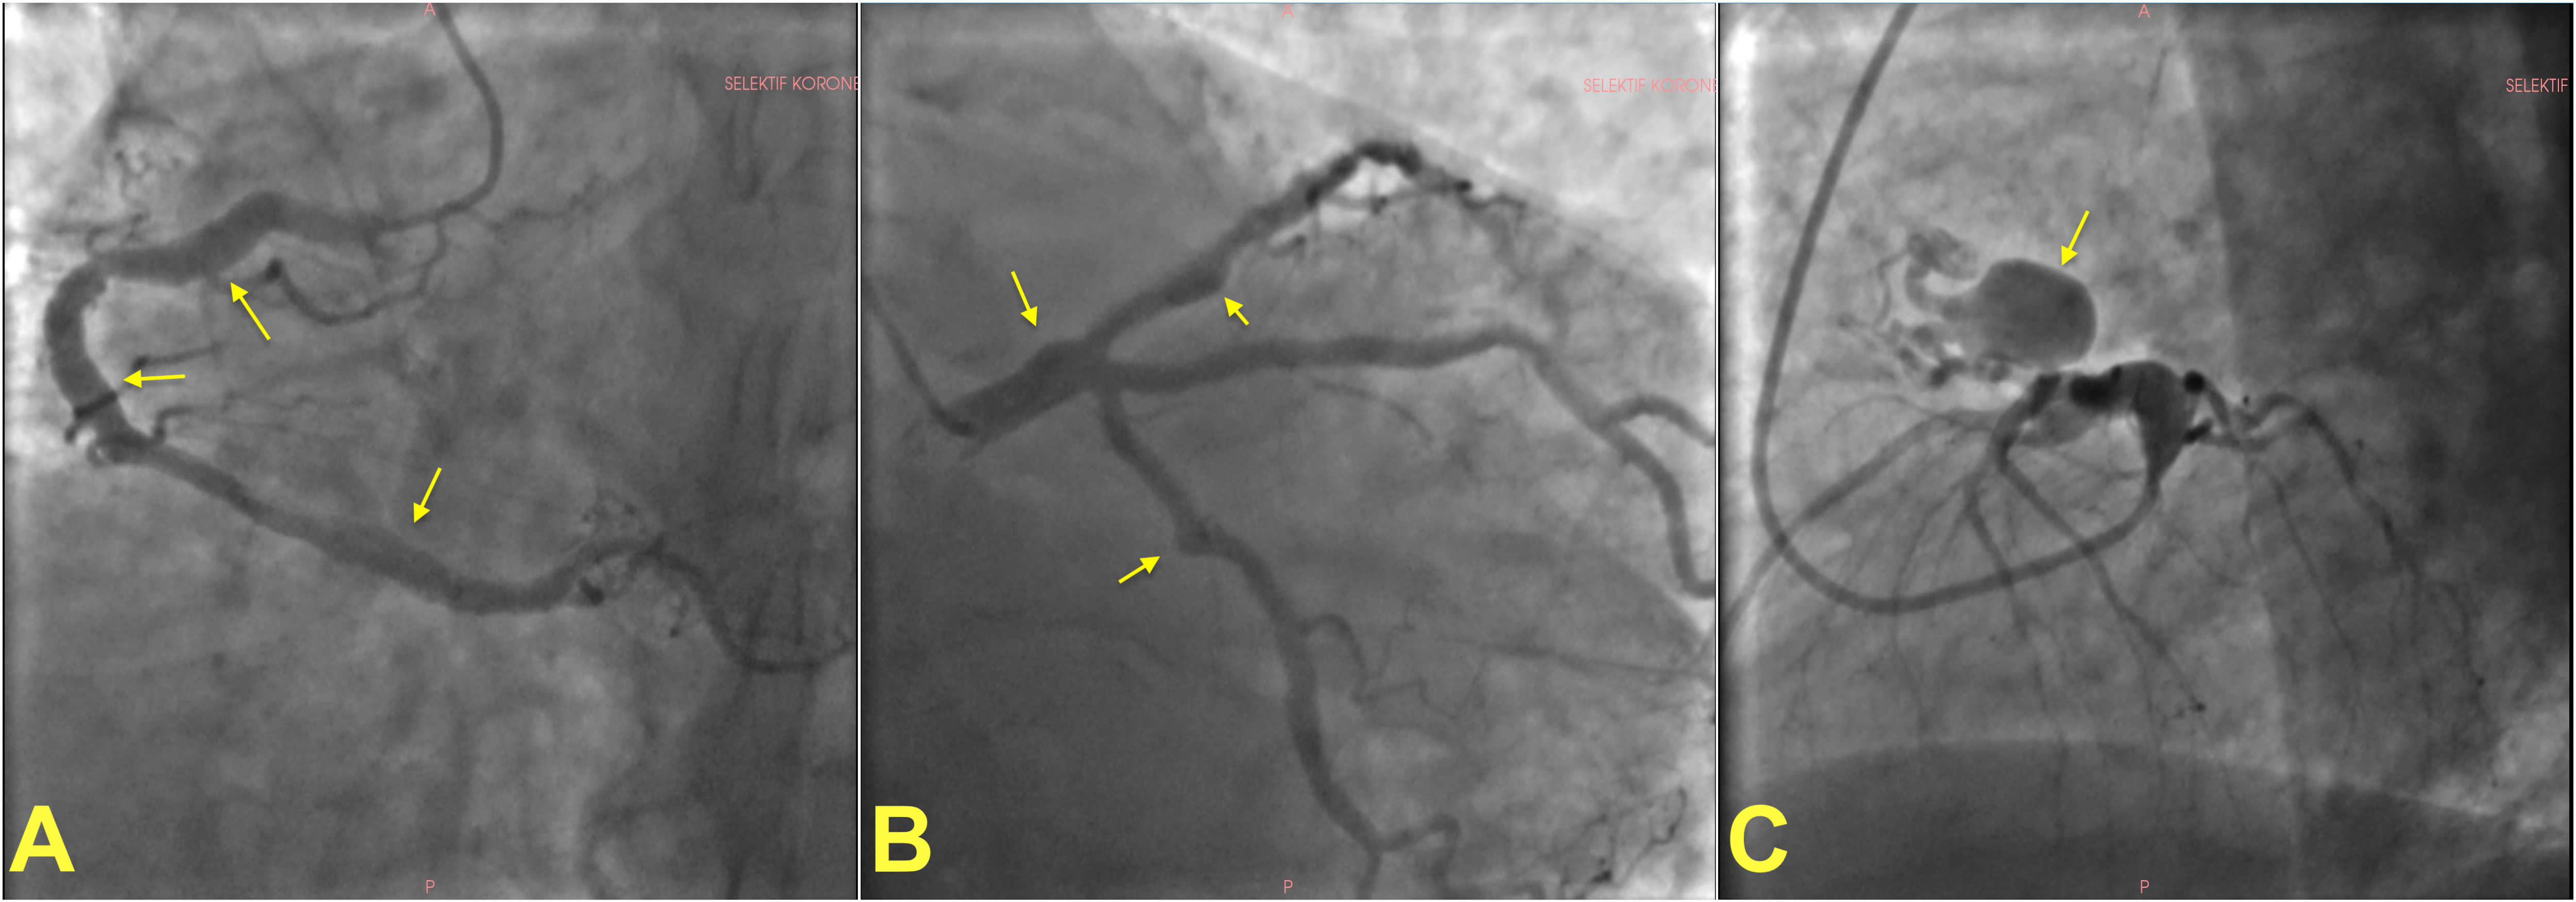

Fig. 1.

Invasive angiographic images showing examples of coronary artery ectasia and aneurysms. (A) shows multiple fusiform atherosclerotic coronary artery aneurysms on the right coronary artery in a patient. Left coronary angiogram of the same patient showing multiple coronary aneurysms on the left main stem, left circumflex and left anterior descending artery (B). A giant saccular aneurysm in a different patient (C). Arrows show aneurysms in all panels.